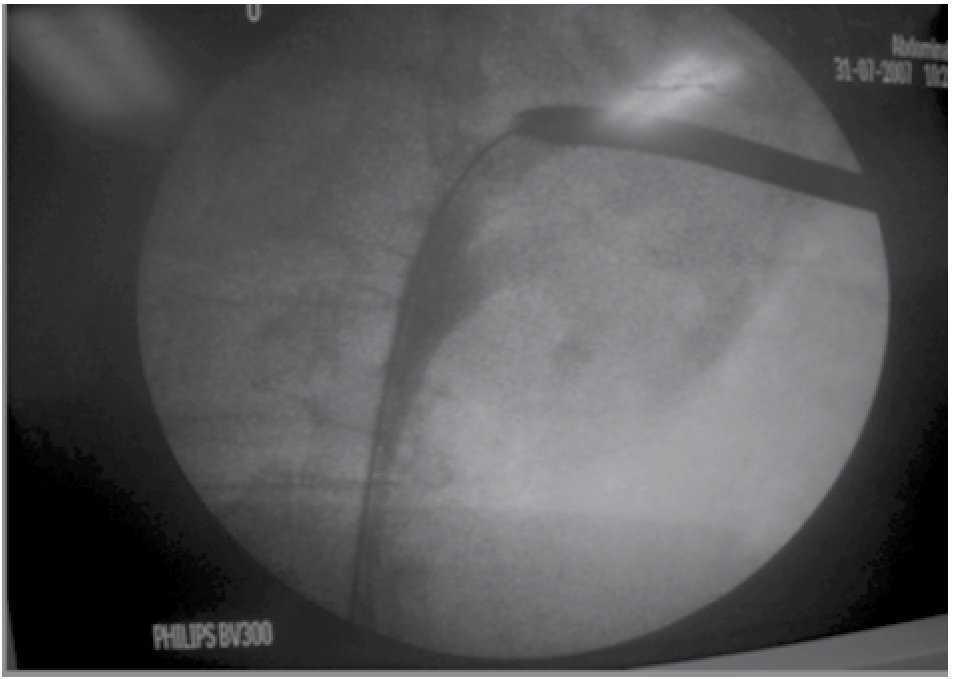

La cirugía fue reportada sin incidentes ni accidentes. En un tiempo de una hora 20 minutos (Figuras 4 y 5). Con una estancia intrahospitalaria posoperatoria de cuatro días. La sonda de nefrostomía del tracto percutáneo se retiró al tercer día.

Figura 4. Imagen de fluoroscopía. Acceso percutáneo intercostal (entre 11ª y 12ª costilla), a través de cáliz superior y dilatación con sistema Amplantz, dilatándose hasta 30Fr.